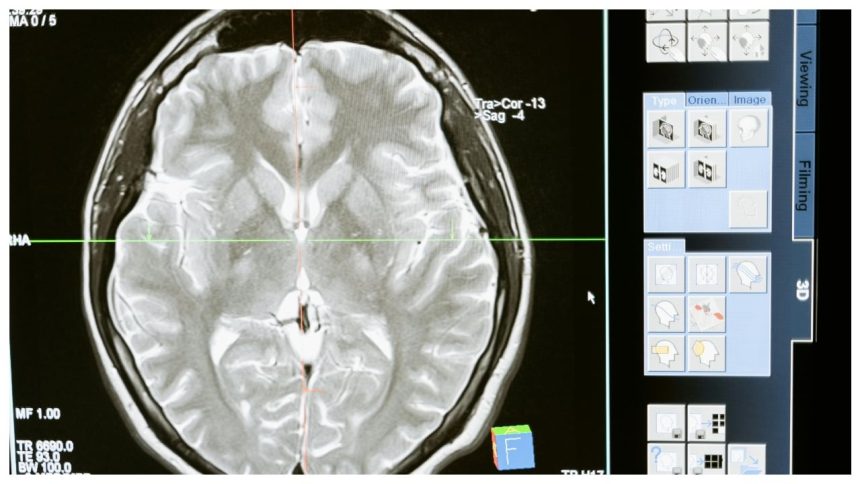

Gliomas are becoming an increasing concern in India due to several factors. The country has witnessed a rise in the number of brain tumor cases, including gliomas, due to improved diagnostic techniques like MRI and CT scans, which help detect these tumors earlier and more accurately. Environmental factors, such as increased exposure to radiation, pollution, and lifestyle changes, are also believed to contribute to the rise in cases. However, more research is needed to fully understand the reasons behind this growing trend.